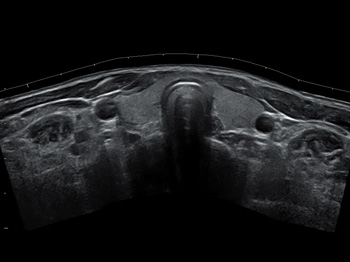

Canon PLT-604AT (10L4) |

Линейный |

4-9,2 МГц |

Поверхностные органы (щитовидная железа, молочная железа, лимфоузлы) Скелетно-мышечная система Периферические сосуды |

Canon PLT-1005BT (14L5) |

Линейный |

4-14 МГц |

Поверхностные органы (щитовидная железа, молочная железа, лимфоузлы) Скелетно-мышечная система Периферические сосуды |

Canon PLT-1204BX (18LX7) |

Линейный |

5-18 МГц |

Поверхностные органы (щитовидная железа, молочная железа, лимфоузлы) Скелетно-мышечная система Периферические сосуды |

Canon PLT-705BT (11L3) |

Линейный |

3-11 МГц |

Поверхностные органы (щитовидная железа, молочная железа, лимфоузлы) Скелетно-мышечная система Периферические сосуды |

Canon PLT-1204BT (18L7) |

Линейный |

5-18 МГц |

Поверхностные органы (щитовидная железа, молочная железа, лимфоузлы) Скелетно-мышечная система Периферические сосуды |